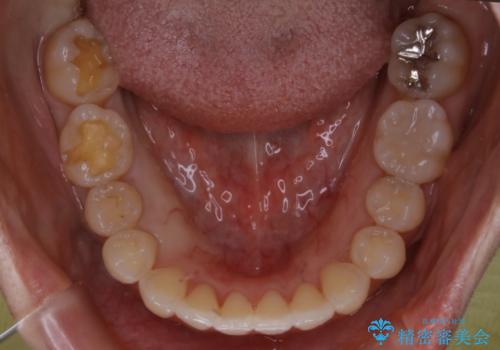

- 矯正治療が終了して歯並びが綺麗になると、元々入っていた銀歯が気になってきたとのことで適合の良いセラミックへのやり替えを行いました。

適合不良の補綴物は二次的な虫歯発生のリスクが高まります。

自費診療で用いられる材料は保険適応の材料に比べて、より精密で適合の良い被せ物作ることができるため、長期的な虫歯のリスクを大幅に減らすことが可能です。